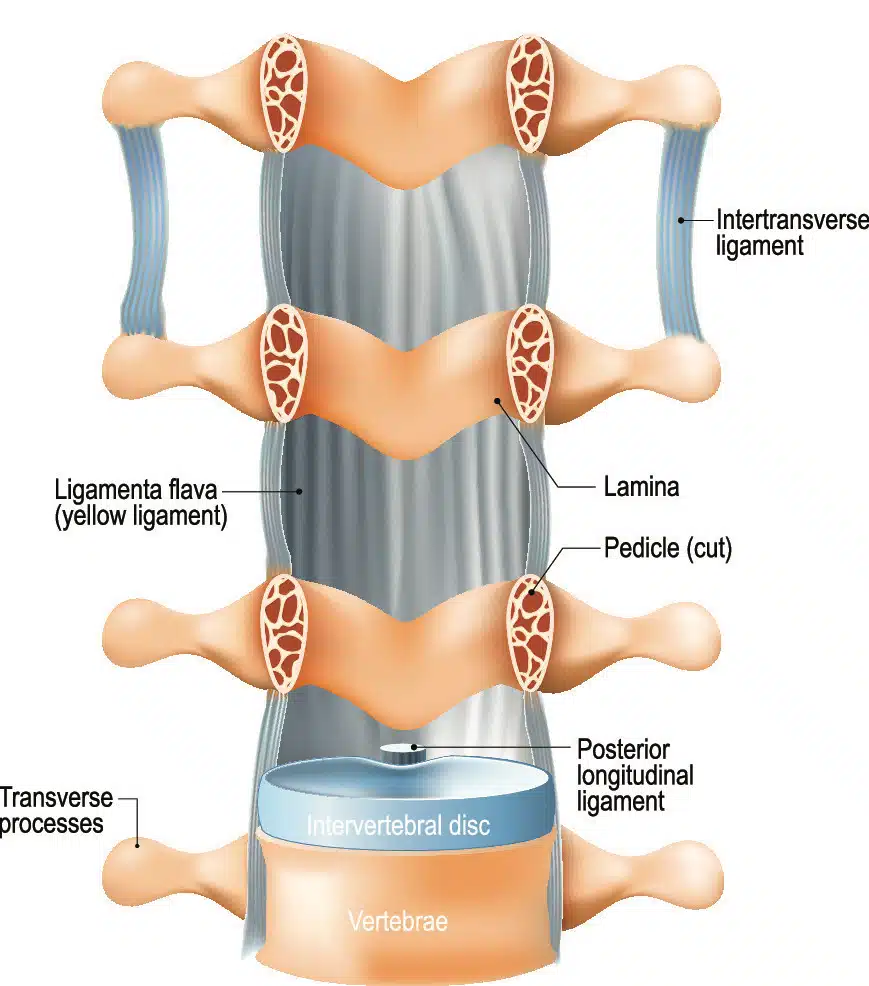

Pure Health - Anatomy 101 - Supraspinous ligament and interspinous ligament 📚 The supraspinous ligament and interspinous ligament work together to limit flexion of the spine by limiting separation of the spinous

DOCS - The interspinous ligament is located between the spinous processes of adjacent vertebrae in the spine. It extends from the base of one spinous process to the apex of the next,